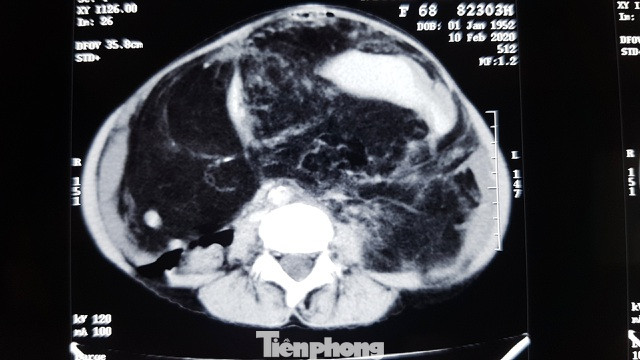

Hình chụp X-quang khối u khủng (phần màu đen) tràn hết trong khoang bụng nữ bệnh nhân

Qua chẩn đoán trước mổ, đây là khối u ổ bụng khổng lồ tái phát, sinh thiết u trước mổ là u mỡ lành tính. Đặc biệt đường kính khối u cực kỳ lớn 30×25 cm chiếm toàn bộ ổ bụng và chèn ép các cơ quan lân cận như: mạch máu mạc treo, ruột non, ruột già…gây biến chứng tắc ruột rõ.